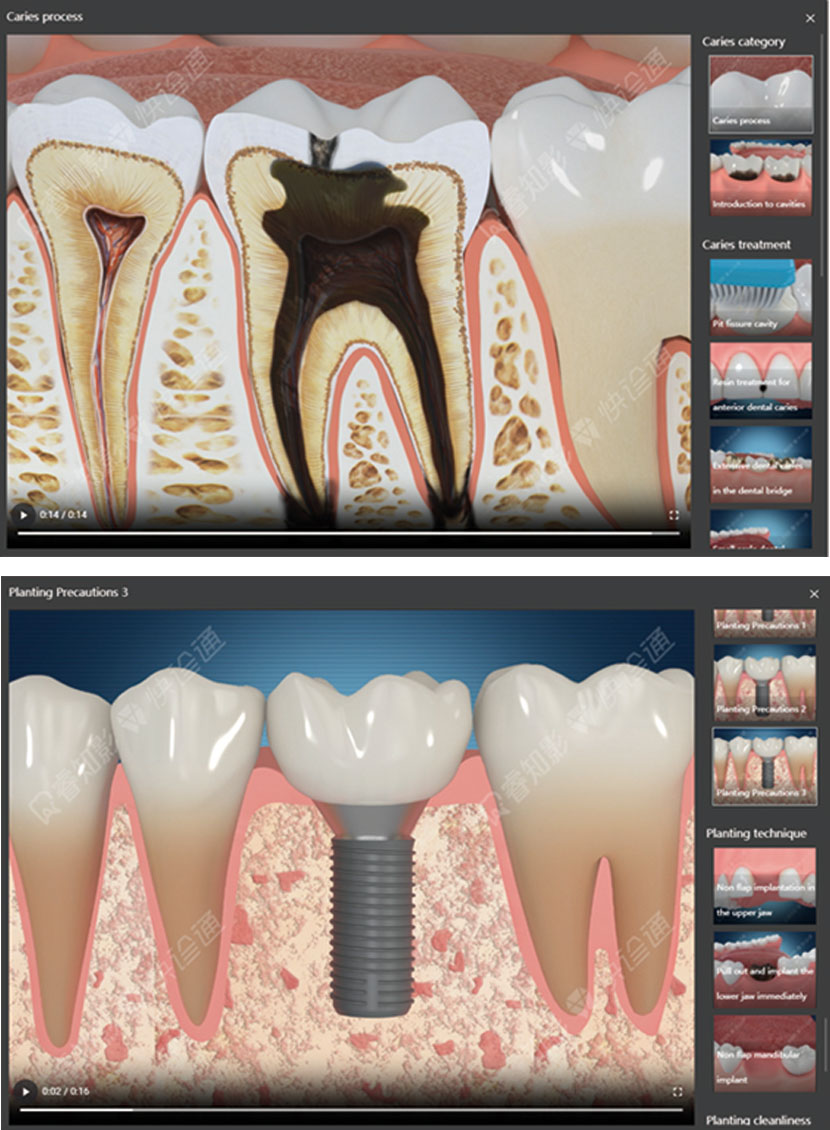

Al-Powered: detección rápida y precisa de enfermedades

Precisión impulsada por IA: visualización óptima de las condiciones

Herramientas mejoradas para la comunicación con los pacientes

Tratamiento y Cirugía de Implantes Impulsados por IA

Herramienta de Planificación de Implantes por IA

La herramienta de planificación impulsada por IA detecta automáticamente los dientes y el nervio alveolar inferior, proporcionando alertas de seguridad en tiempo real. Soporta medición automática, simulación de implantes y optimización de trayectoria, lo que permite una planificación de tratamiento rápida y precisa.

Diseño de Guía Quirúrgica por IA

El módulo de guía quirúrgica de IA diseña automáticamente guías en un plazo de tres minutos. Los clínicos simplemente revisan y exportan los datos, con archivos STL e informes generados al instante, asegurando eficiencia y enfoque durante la cirugía.